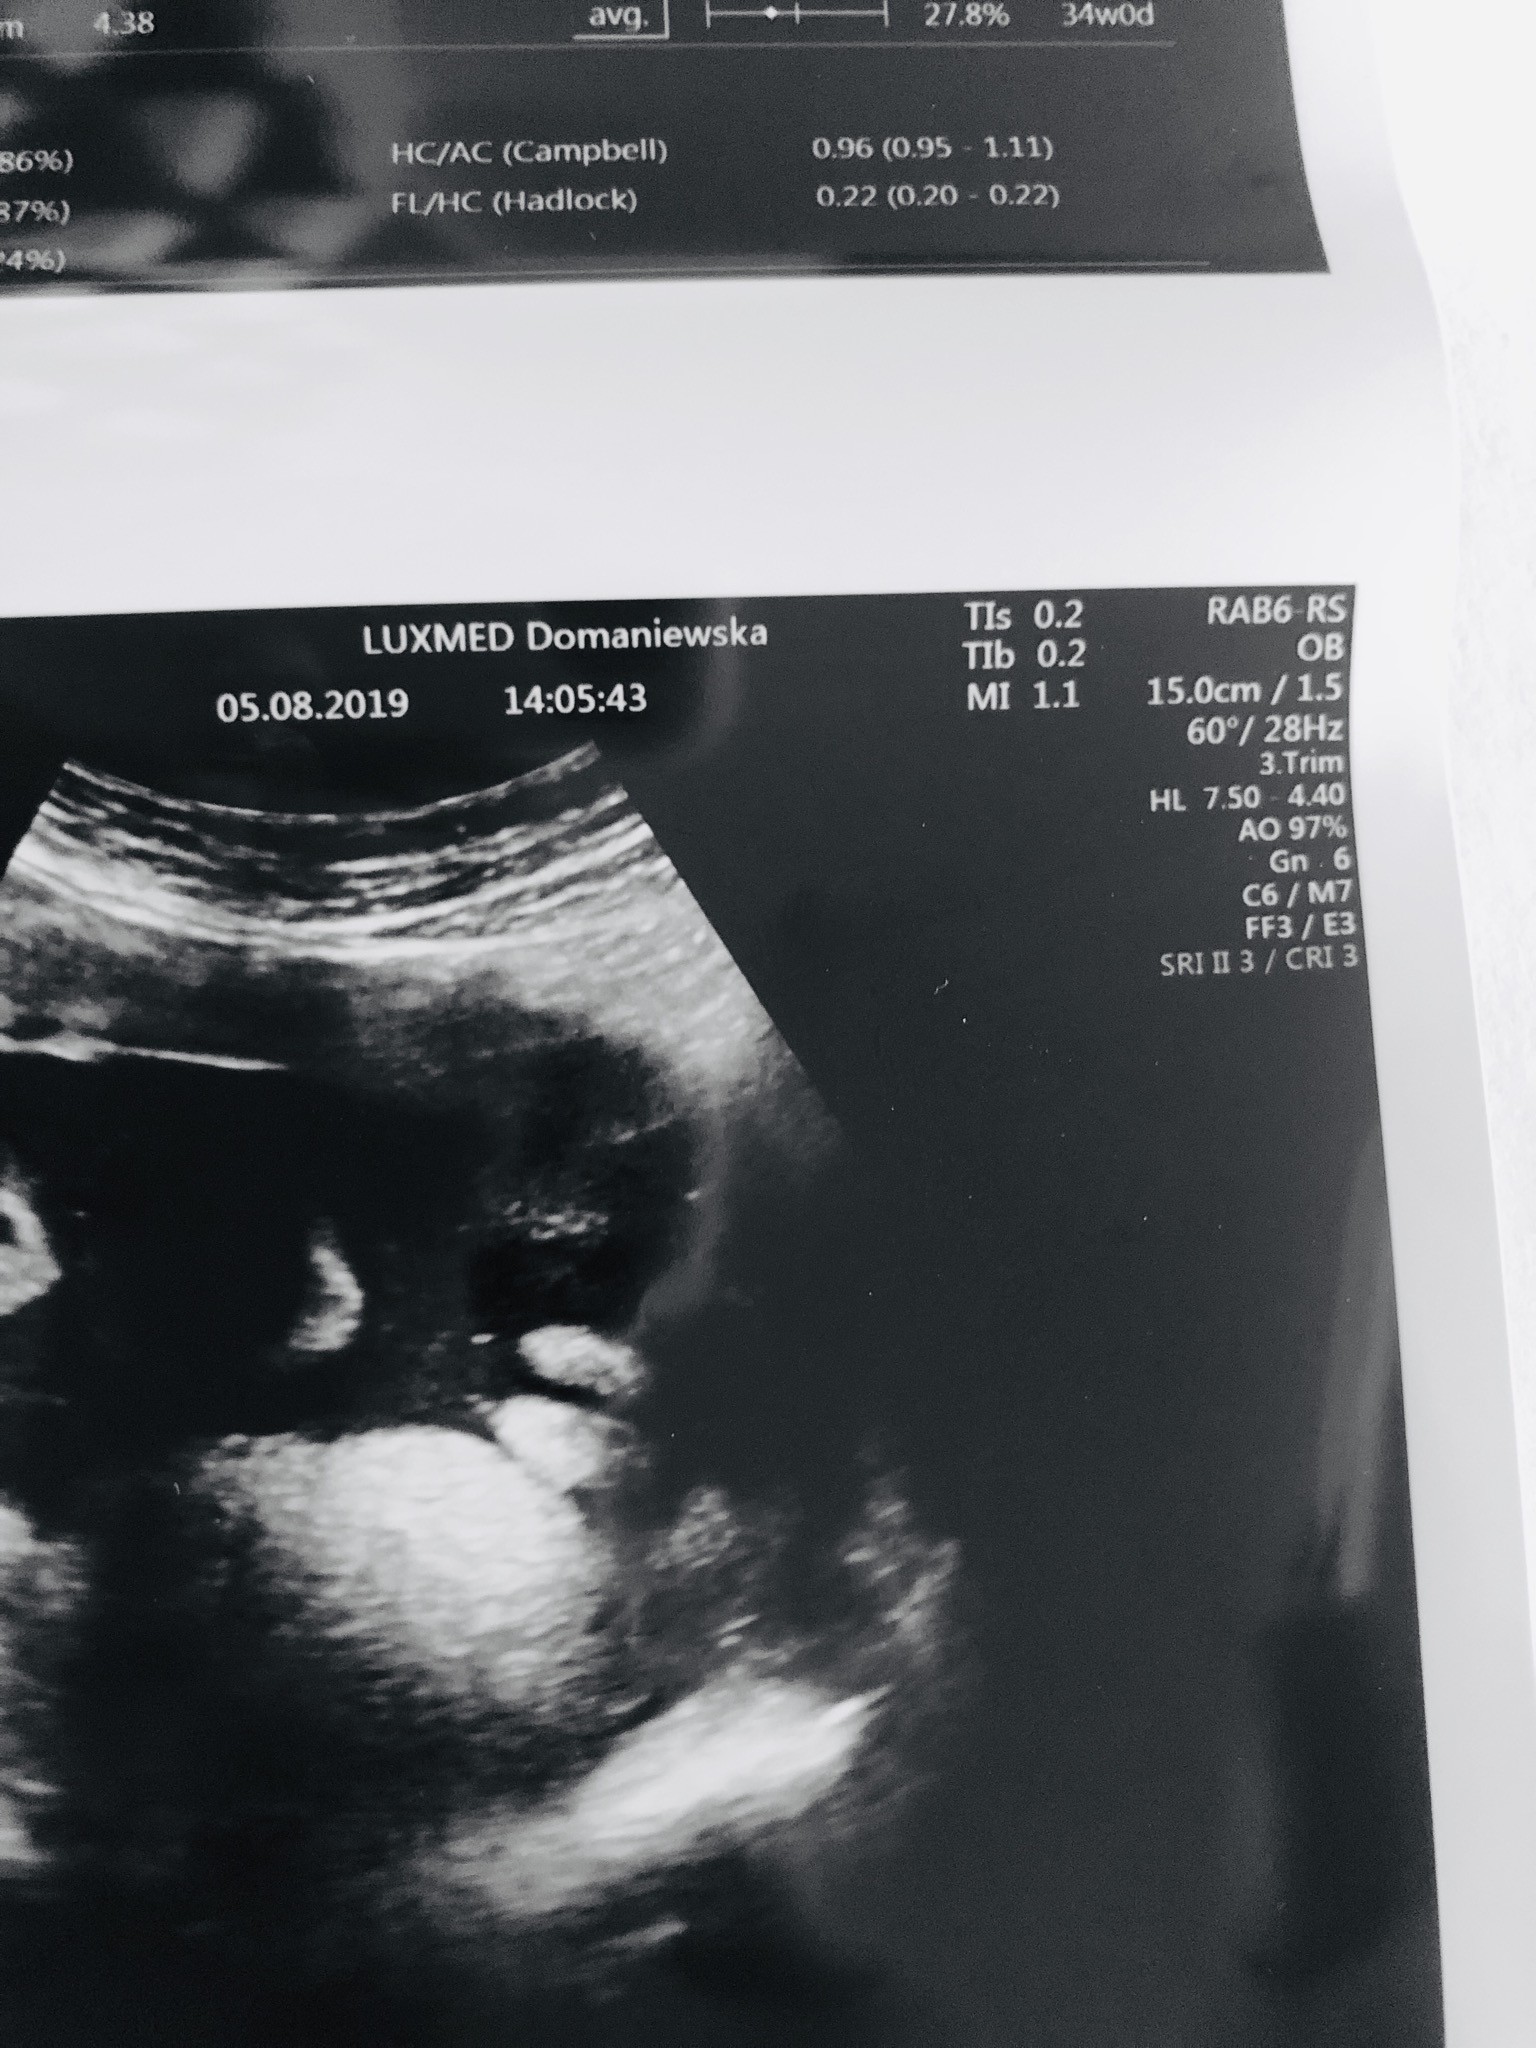

Dziewczyny a czy to na pewno nie moszna ? Zdjęcie koleżanki która oczekuje córeczki ale bodajże w 33tc usg lekarz stwierdził ze chyba coś dynda ale nie mógł uchwycić a później dostała takie zdjęcie.

To są wargi ?

• 238079B3-D2C5-4729-8B5C-0B0B1AE4F8FA.jpeg

238079B3-D2C5-4729-8B5C-0B0B1AE4F8FA.jpeg

550,2 KB · Wyświetleń: 420